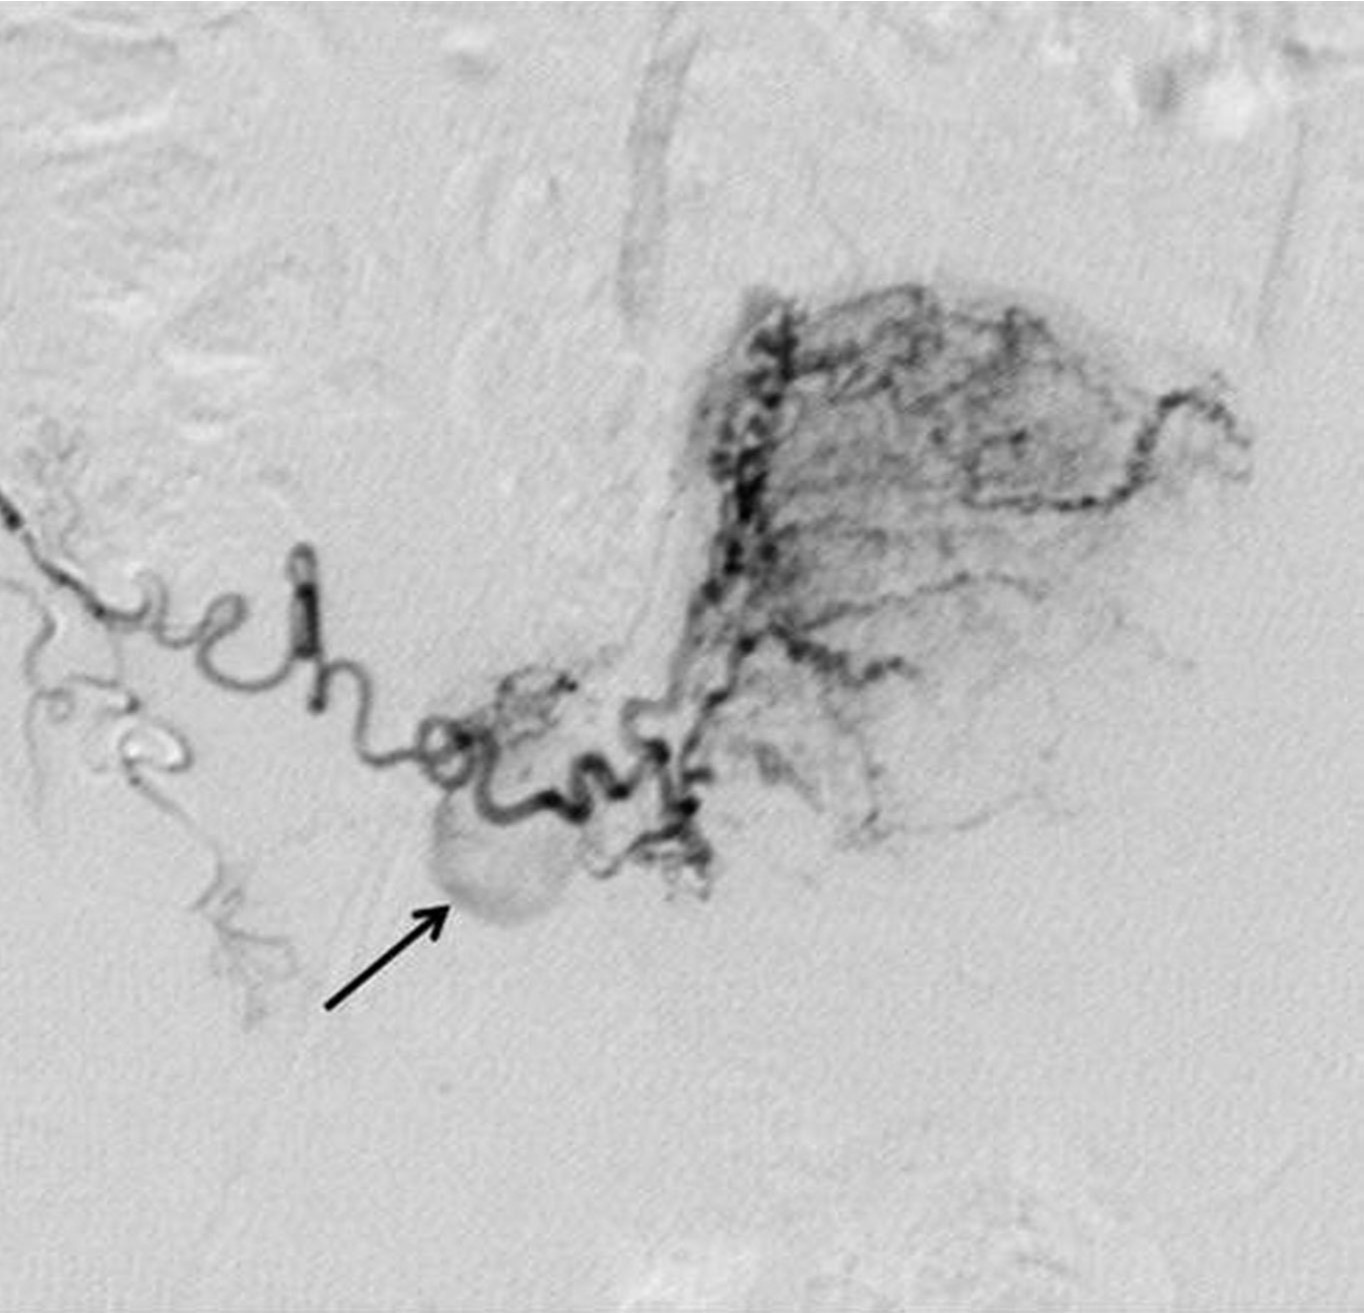

Fig. 2. C

Fig. 2A-C. Pelvic angiogram (A) shows the tortuous and dilated left uterine artery (arrow) and atrophy of the right uterine artery. An aberrant ovarian collateral (arrowhead) originates from the right external iliac artery. Selective right external iliac angiogram (B) reveals the aberrant ovarian collateral (thin arrow), right inferior epigastric(thick arrow), and right round ligament(arrowhead) arteries. Selective aberrant ovarian collateral angiogram (C) demonstrates that the collateral supplies blood flow to the right half of the uterus as well as the right ovary (arrow).